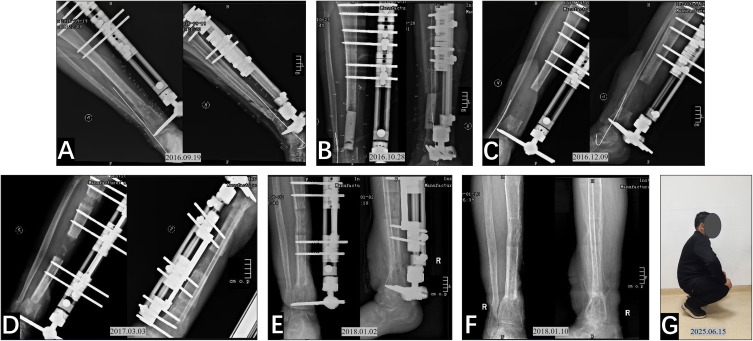

Methods: In this retrospective observational single-arm study, we analyzed the clinical data of 22 patients who had undergone multiple debridements for refractory distal tibial osteomyelitis (DTO) and had associated bone defects, and were subsequently treated with the Ilizarov bone transport technique. Following debridement surgery, bone transport treatment was administered. Regular X-ray examinations, rehabilitation guidance, and follow-up were conducted to assess infection control, bone healing, limb function recovery, and complications. Therapeutic effects were evaluated using the Association for the Study and Application of Methods of Ilizarov (ASAMI), Visual Analog Scale (VAS) score, Activities of Daily Living (ADL) score, and American Orthopaedic Foot & Ankle Society (AOFAS) score improvement.

Results: The mean follow-up was 29.32±20.92 months, with an average of 3.77±1.83 debridements. All bone defects healed, though 5 patients later required ankle arthrodesis. Complications included pin tract infection (n=10), axial deviation (n=3), ankle joint stiffness (n=2), non-union at the docking site (n=2), and delayed consolidation (n=2). At the last follow-up, ASAMI bone results: 15 excellent, 5 good, 2 poor (90.9% superiority rate). ASAMI functional results: 6 excellent, 14 good, 1 fair, 1 poor (90.9% superiority rate). VAS decreased from 4.86±0.83 to 0.5±0.66 (p<0.001). ADL improved from 80 (78.75-85) to 92.5 (90-95) (p<0.001). AOFAS score increased from 32 (25-38.25) to 82 (77-87.5) (p<0.001), with an 86.4% overall superiority rate.

Abstract Image